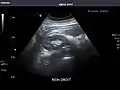

Left kidney

Kidneys: Right and left kidneys measure 11.5 cm and 12 cm in length respectively. No hydronephrosis. Small left lower pole kidney cyst.